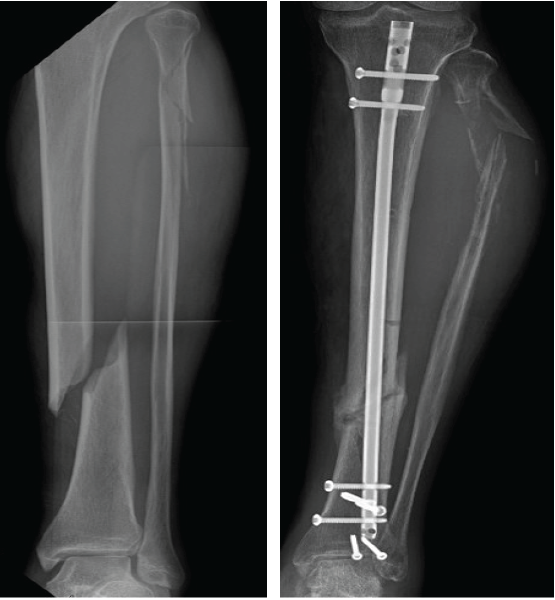

A 56-year-old male presented to the emergency department of our institution with worsening swelling and pain in his left lower extremity. Eight months prior, he had sustained fractures of the left mid-tibial shaft, proximal fibular shaft, and posterior malleolus after dropping a piece of plywood on his leg (Fig. 1a). Initial management involved closed reduction of the tibial shaft fracture with the application of a uniplanar external fixator, alongside open reduction and internal fixation of the posterior malleolus fracture. Subsequently, the tibial fracture was stabilized with intramedullary nailing, and the external fixator was removed. Additional blocking screws were placed proximally and distally to maintain alignment and prevent varus collapse. Two proximal interlocking screws were inserted in a medial-to-lateral direction using an outrigger jig (Fig. 1b). No significant bleeding or acute swelling was noted intraoperatively or in the immediate post-operative period. Routine follow-up examinations revealed swelling and stiffness, which were initially considered expected findings given the high-energy nature of the injury and extensive soft tissue involvement. A peripheral venous Doppler study was performed following external fixation and showed no evidence of thrombosis. However, the assessment was limited due to the presence of a large cutaneous wound and bandaging.

Figure 1: (a) Pre-operative radiograph reveals acute, mildly comminuted fractures of the mid/distal tibia and proximal fibular shaft. (b) Post-operative radiograph reveals intramedullary nailing of tibial shaft fracture in improved alignment and proximal fibular shaft fracture with increased displacement and apex posterior angulation. Upon the present presentation with the increased lateral calf pain and swelling, Doppler ultrasound revealed a large pseudoaneurysm of the ATA with the characteristic yin-yang sign (Fig. 2). CTA confirmed a pseudoaneurysm arising from the proximal ATA, surrounded by a large hematoma in the leg (Fig. 3). The largest aneurysmal sac measured approximately 8.7 × 10.4 × 16.1 cm, with an actively filling, non-thrombosed component measuring about 3.4 × 3.8 × 6.5 cm. Given the significant compressive symptoms caused by the hematoma, coil embolization of the ATA was performed to exclude blood flow into the pseudoaneurysm cavity. Selective catheterization of the left ATA was achieved through ultrasound-guided puncture of the right common femoral artery. Multiple Penumbra Ruby coils were deployed into the proximal and distal segments of the ATA, effectively sealing the pseudoaneurysm defect. A pre- and post-procedural angiogram demonstrated successful cessation of blood flow into the pseudoaneurysm cavity (Fig. 4a and b).